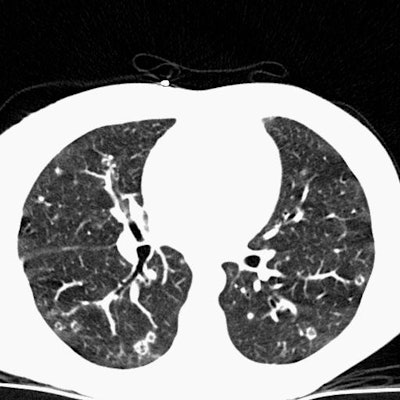

Scott WilliamsThoracic ImagingAutoimmuneAutoimmune > EG > Images > Case3Scott WilliamsApr 2, 2002 Eosinophilic Granuloma Case 3: In this example of pulmonary eosinophilic granuloma. Computed tomography of the chest demonstrated multiple thin walled cysts, cavitating nodules, and scattered non-cavitary nodules. Latest in AutoimmuneAutoimmune > Hyalinizing granulomaOctober 19, 2020Autoimmune > DrugsOctober 19, 2020Autoimmune > DrugsMarch 12, 2018Autoimmune > EG > Images > Case5July 31, 2011Related StoriesAutoimmuneAutoimmune > Lymphomatosis > Images > Case1AutoimmuneAutoimmune > Sarcoid > Images > Sarcoid7AutoimmuneAutoimmune > IPFibrosis > UIPimages > Case1AutoimmuneAutoimmune > Sarcoid > Images > Sarcoid1B